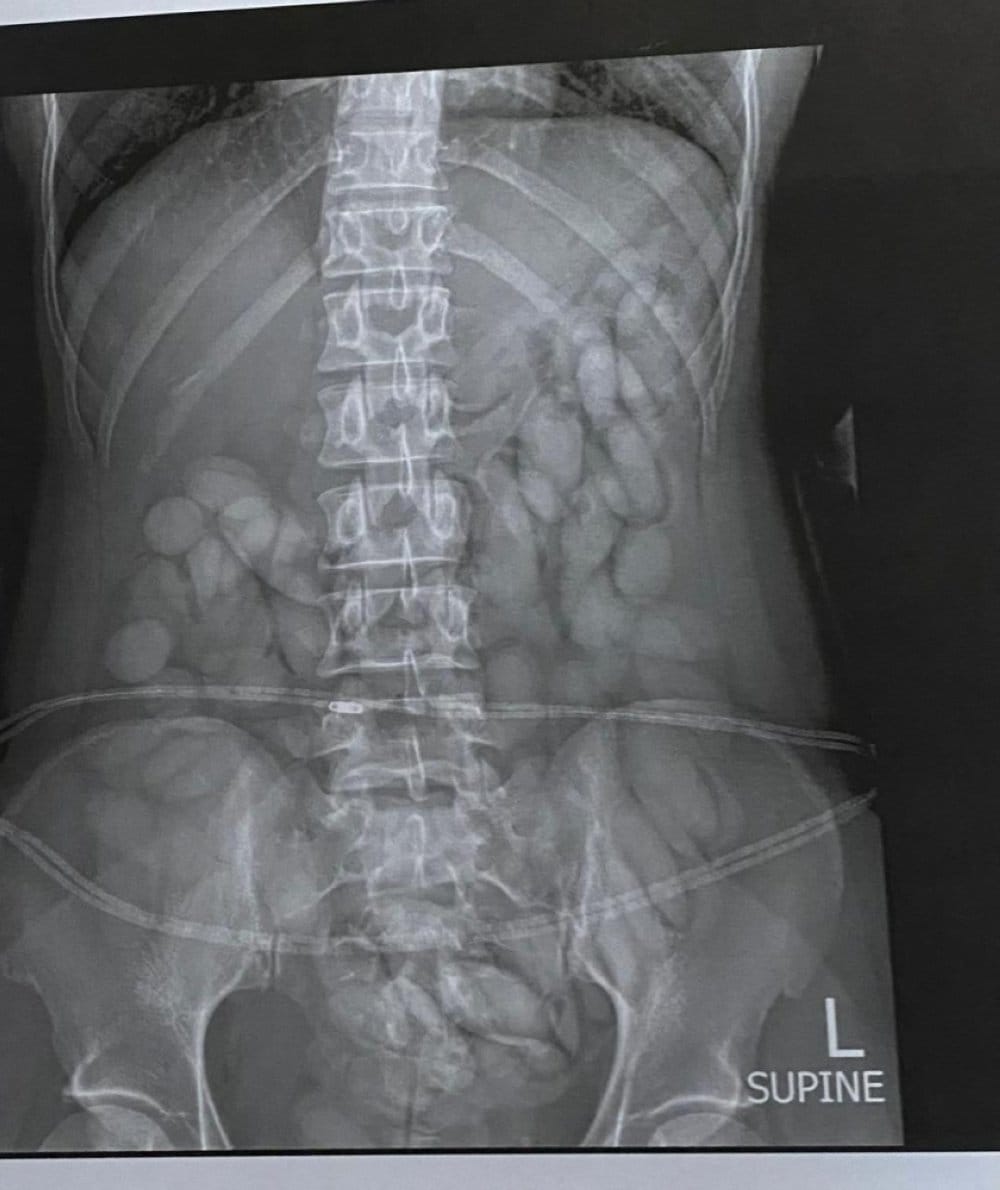

After her arrest, the woman nabbed with stomach full of drugs was taken to a hospital where X-rays confirmed she had swallowed drug bullets.

Mbangula eventually expelled 68 pellets weighing 850 grams. SAPS spokesperson Brigadier Athlenda Mathe confirmed that Mbangula was moved to a detention facility after all the drugs were removed from her system. She is due to appear in the Kempton Park Magistrate’s Court on drug dealing and possession charges.